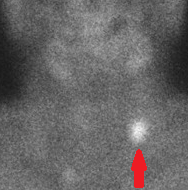

PET scan. Εμφανής η υπερμεταβολική εστία στον δεξιό μαστό (Ευγενική παραχώρηση Dr. V. Penopoulos)